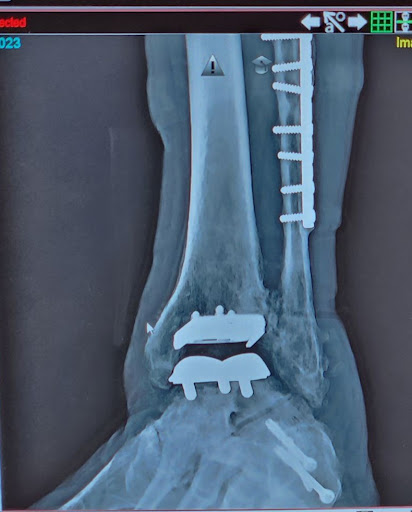

May 25, 2024Master at his craft! Dr Hegewald did a left ankle replacement, and a right ankle fusion for my husband. He is now able to walk with minimal pain for the 1st time in years! Thank you Dr Hegewald for getting him mobile again! As my husband would say "Dr H.... read more Is the man!"